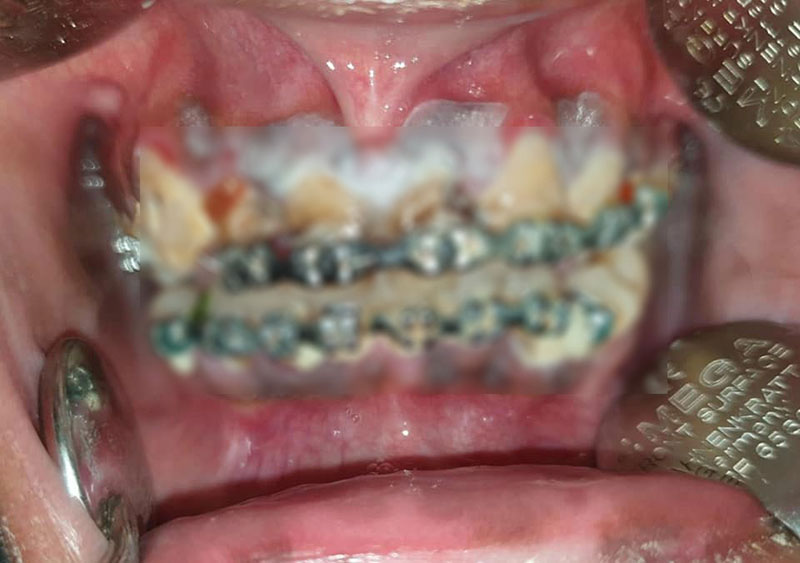

ล่าสุด (20 กุมภาพันธ์ 2563) เรื่องเล่าเช้านี้ ได้สอบถามไปยังคุณหมอที่โพสต์ภาพดังกล่าว ชื่อ ทันตแพทย์หญิงพรพุทธิ ภัทรวุฒิพร ทันตแพทย์เฉพาะทางด้านจัดฟัน โรงพยาบาลบุรีรัมย์ ซึ่งเผยว่า คนไข้รายนี้อายุ 23 ปี ต้องการนำลวดและอุปกรณ์จัดฟันออก ซึ่งเจ้าตัวจัดมาแล้ว 5 ปี ที่ร้านจัดฟันแฟชั่นแห่งหนึ่งในกรุงเทพฯ

เมื่อตรวจช่องปากก็พบว่า เป็นเครื่องมือไม่ได้มาตรฐาน ส่งผลให้เกิดคราบสีขาว ซึ่งเป็นเชื้อราเกาะอยู่บริเวณเหงือกทั่วทั้งปาก จึงได้ทำความสะอาดและขูดหินปูน พร้อมกับสอนวิธีแปรงฟันอย่างถูกต้อง